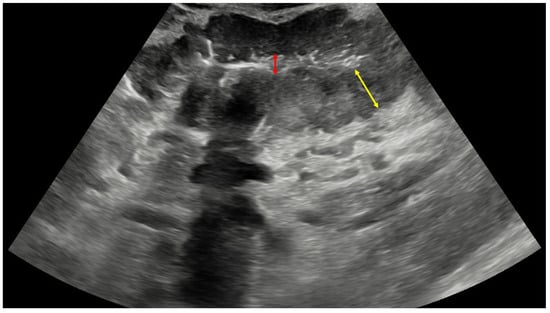

A 75-year-old male patient presented in the emergency department with a 2-month history of dull pain in the epigastric region, followed by loss of appetite, multiple episodes of postprandial vomiting, and 10 kg weight loss during that period. The patient also consumed a small amount of alcohol daily for years and had a 50-pack-year smoking history. Otherwise, his medical record had no active medical treatments or serious illnesses. During clinical examination, the main finding was palpable abdominal resistance in the left upper abdominal quadrant. After laboratory blood and urine sampling, the patient was referred to a transabdominal ultrasound (US). The US demonstrated a well-vascularized mass in the left upper abdominal quadrant, measuring 4.1 × 10.1 × 9.4 cm, presenting with a reniform appearance and hyperechoic center surrounded by a thick hypoechoic wall. The described findings were characteristic of PKS (Figure 2). Regional lymphadenopathy was also detected, and the working diagnosis of gastric cancer was established.

Figure 2. Ultrasound image of pseudokidney sign in this patient with the centrally located hyperechoic gastric lumen (red arrow) surrounded by hypoechoic and thickened gastric wall (yellow arrow), indicative of gastric cancer. Additional findings that may be present in such cases are hypervascularity of the mass, enlarged lymph nodes, and hyperechoic surrounding mesenteric fat.